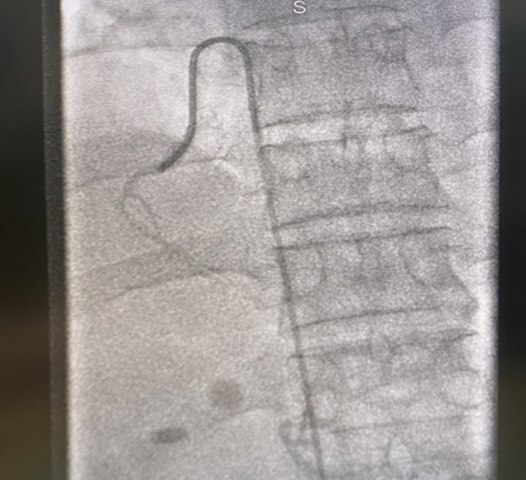

完善肾上腺增强CT提示左侧肾上腺结节灶伴轻度强化,大小约13*15mm,腺瘤。

图片

虽然诊断仍不明确,问题还没解决!孙女士的肾上腺CT提示右侧肾上腺有增粗,到底谁才是元凶?